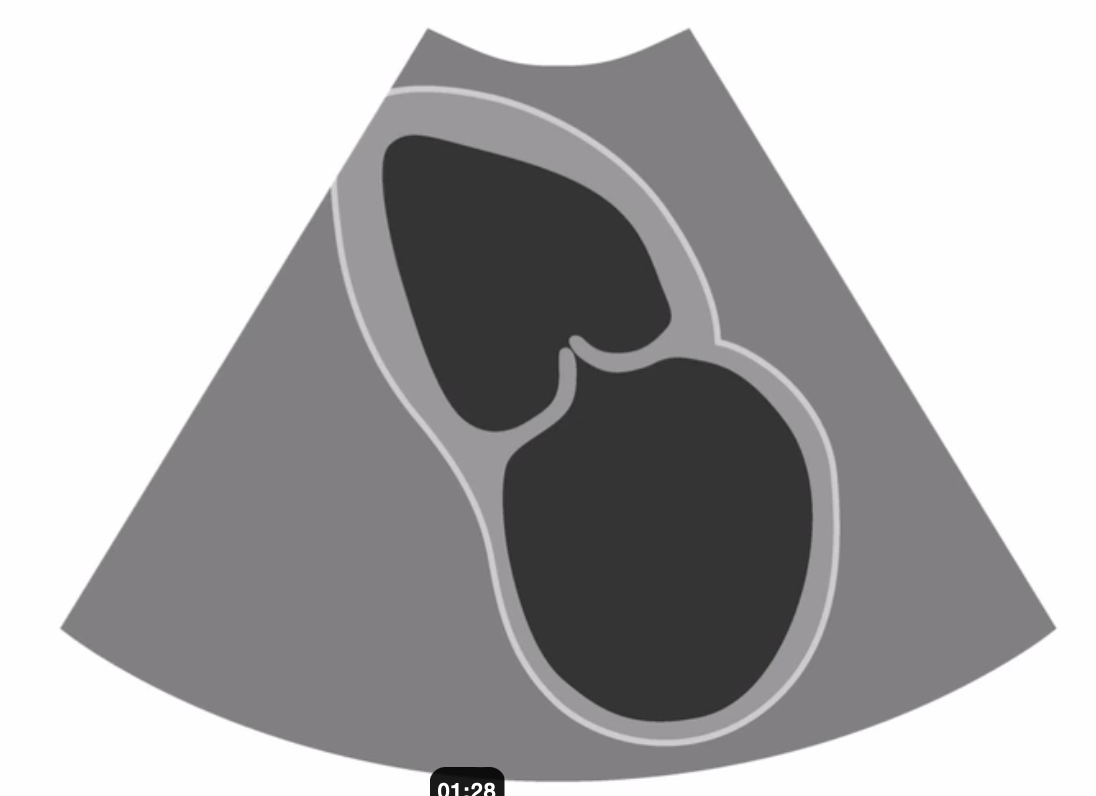

what view are you trying to obtain?

A

PLAX inflow view